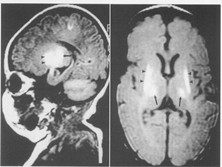

新生儿颅内出血

新生儿颅内出血是新生儿常见的严重疾病,是一种常见的脑损伤,是由产伤和缺氧引起的,...

检查项目:

血常规、脑脊液检测、头部B超、头部CT、血液生化检测